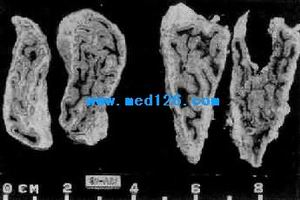

3.腎上腺皮質腺癌的診斷在腎上腺意外瘤中腎上腺皮質腺癌的頻率為0~25%,平均約4%。在Mayoclinic報導的342例腎上腺意外瘤中。只有4例(1.2%)無功能的腎上腺皮質腺癌。在一組義大利多中心經手術的887例腎上腺意外瘤中,腎上腺皮質腺癌約12%。在影像檢查中,腎上腺皮質腺癌一般都比較大,90%以上直徑>6cm,質地不均一,邊緣不規則。常常浸潤到周邊的臟器組織,還可轉移到淋巴結、肺、骨、肝和腎,去氫表雄酮硫酸脂(DHEA-S)測定對鑑別良惡性有一定幫助,良性腫塊DHEA-S多數低於正常,惡性者高於正常,但兩組病人有重疊。DHEA-S水平升高者應考慮腎上腺意外瘤有分泌腎上腺性激素的可能。